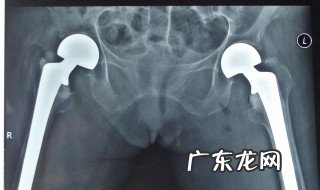

2、如果局部出现疼痛,肿胀等不适,建议到医院就诊行x线片检测,以了解有没有尾骨骨折和脱位,如果有尾骨脱位,可给予尝试手法复位,如果有尾骨骨折移位,如果移位不是很严重者,常常采取保守治疗,保守治疗,可卧床休息,6到8周左右骨折即可愈合,卧床的时候避免是睡太软的床铺 。避免尾骨部位受压刺激,尽量以侧卧位为主 。